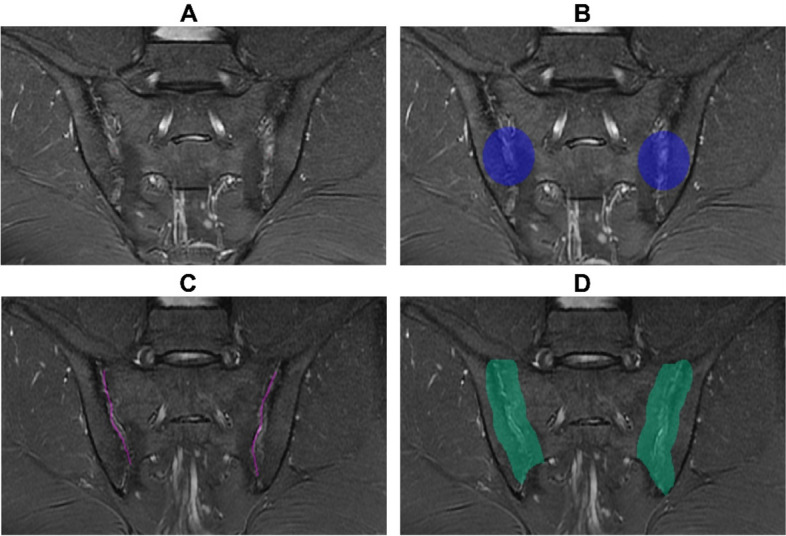

All the expanded ROI boundaries were further validated and corrected by Reader B, to reduce possible bias and to better adhere to the segmentation criteria. An example of SIJ-MRI segmentation and expansion is shown in Fig. 3.

Fig. 3.

SIJ-MRI segmentation and expansion for four ROIs: CircleOriginal (A), Circle (B), Facet (C), and FacetOriginal (D). MR, magnetic resonance; SIJ, sacroiliac joint